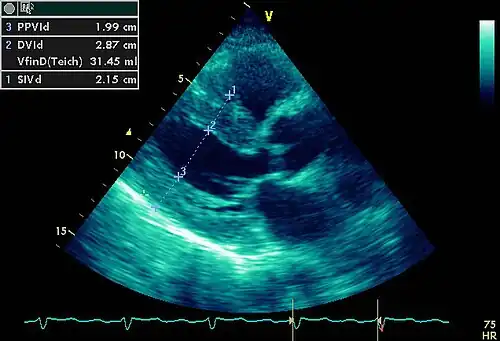

- Ecocardiograma dóppler-color. Estudio no invasivo de altísimo rendimiento diagnóstico. No es un estudio de primer nivel porque requiere de equipo sofisticado y personal altamente entrenado, por lo que su costo es relativamente alto. No se recomienda la ecocardiografía de rutina en pacientes con hipertensión sin síntomas o evidencia clínica de daño orgánico cardíaco.